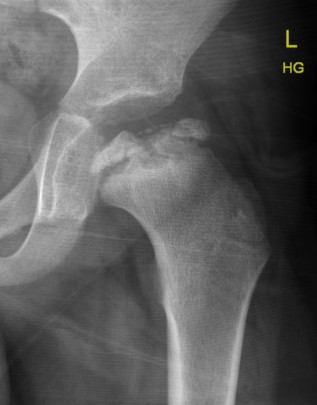

Valgus femoral osteotomy

Concept

Hinge abduction

- move medial, better-preserved part of the femoral head into the loading zone

- reduce adduction contracture and distalize the greater trochanter